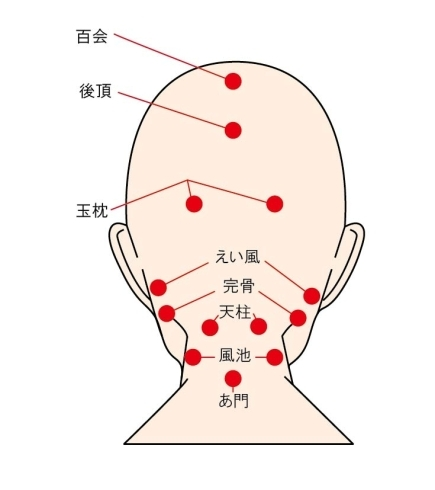

こんにちはいろは整堂です🍀 よく 首が痛くなる 凝るという方 多いですよね(>_<) 現代では 首の不調の原因の一つとしてよく聞くのが スマホやパソコン作業 世間では ブルーライトがスマホ弊害として挙げられますが それよりも 首を前にして見る姿勢 いわゆる ストレートネックと呼ばれる姿勢が悪さをしている事が多々あります💧 街中でもこういった姿勢になっている人多くみませんか? ストレートネックは 首の後ろにある筋肉にものすごく負担をかけます❗...